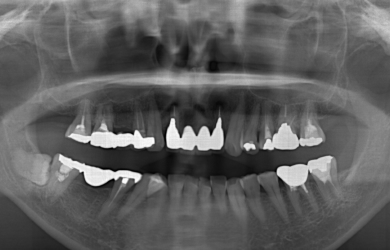

治療方針 ブリッジの支えとなっている歯の寿命を延ばすため、ブリッジの部分を切断し、インプラント治療を施す。

治療内容 インプラント1本、ハイブリッドセラミック1本、ジルコニアオールセラミック8本

治療前

• 治療前